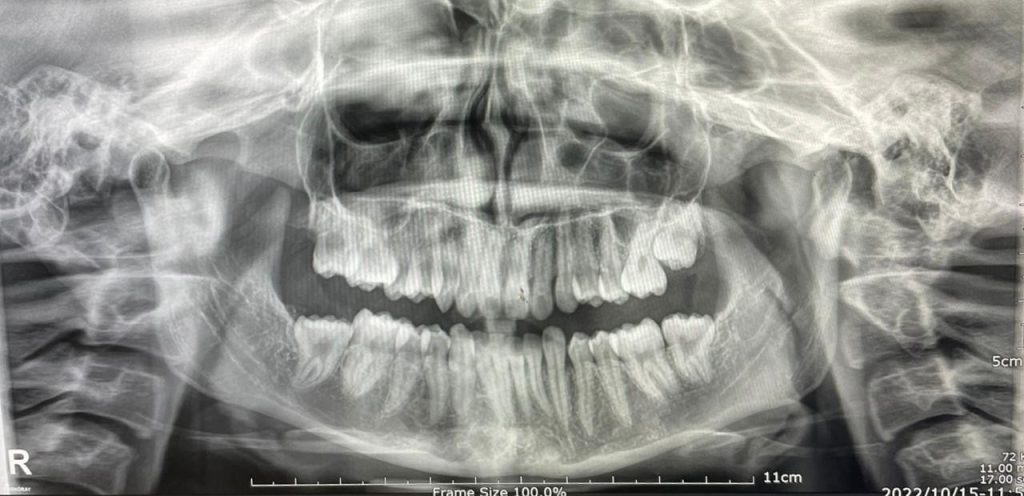

Clinical Findings:

- Mouth opening: 29 mm with leftward deviation

- Muscle tenderness: Masseter, temporalis, lateral pterygoids

- Bite: Deep bite, contributing to dysfunction

- TMJ clicking on the left side

- MRI: Bilateral Disc Displacement Without Reduction (DDwoR) and joint strain